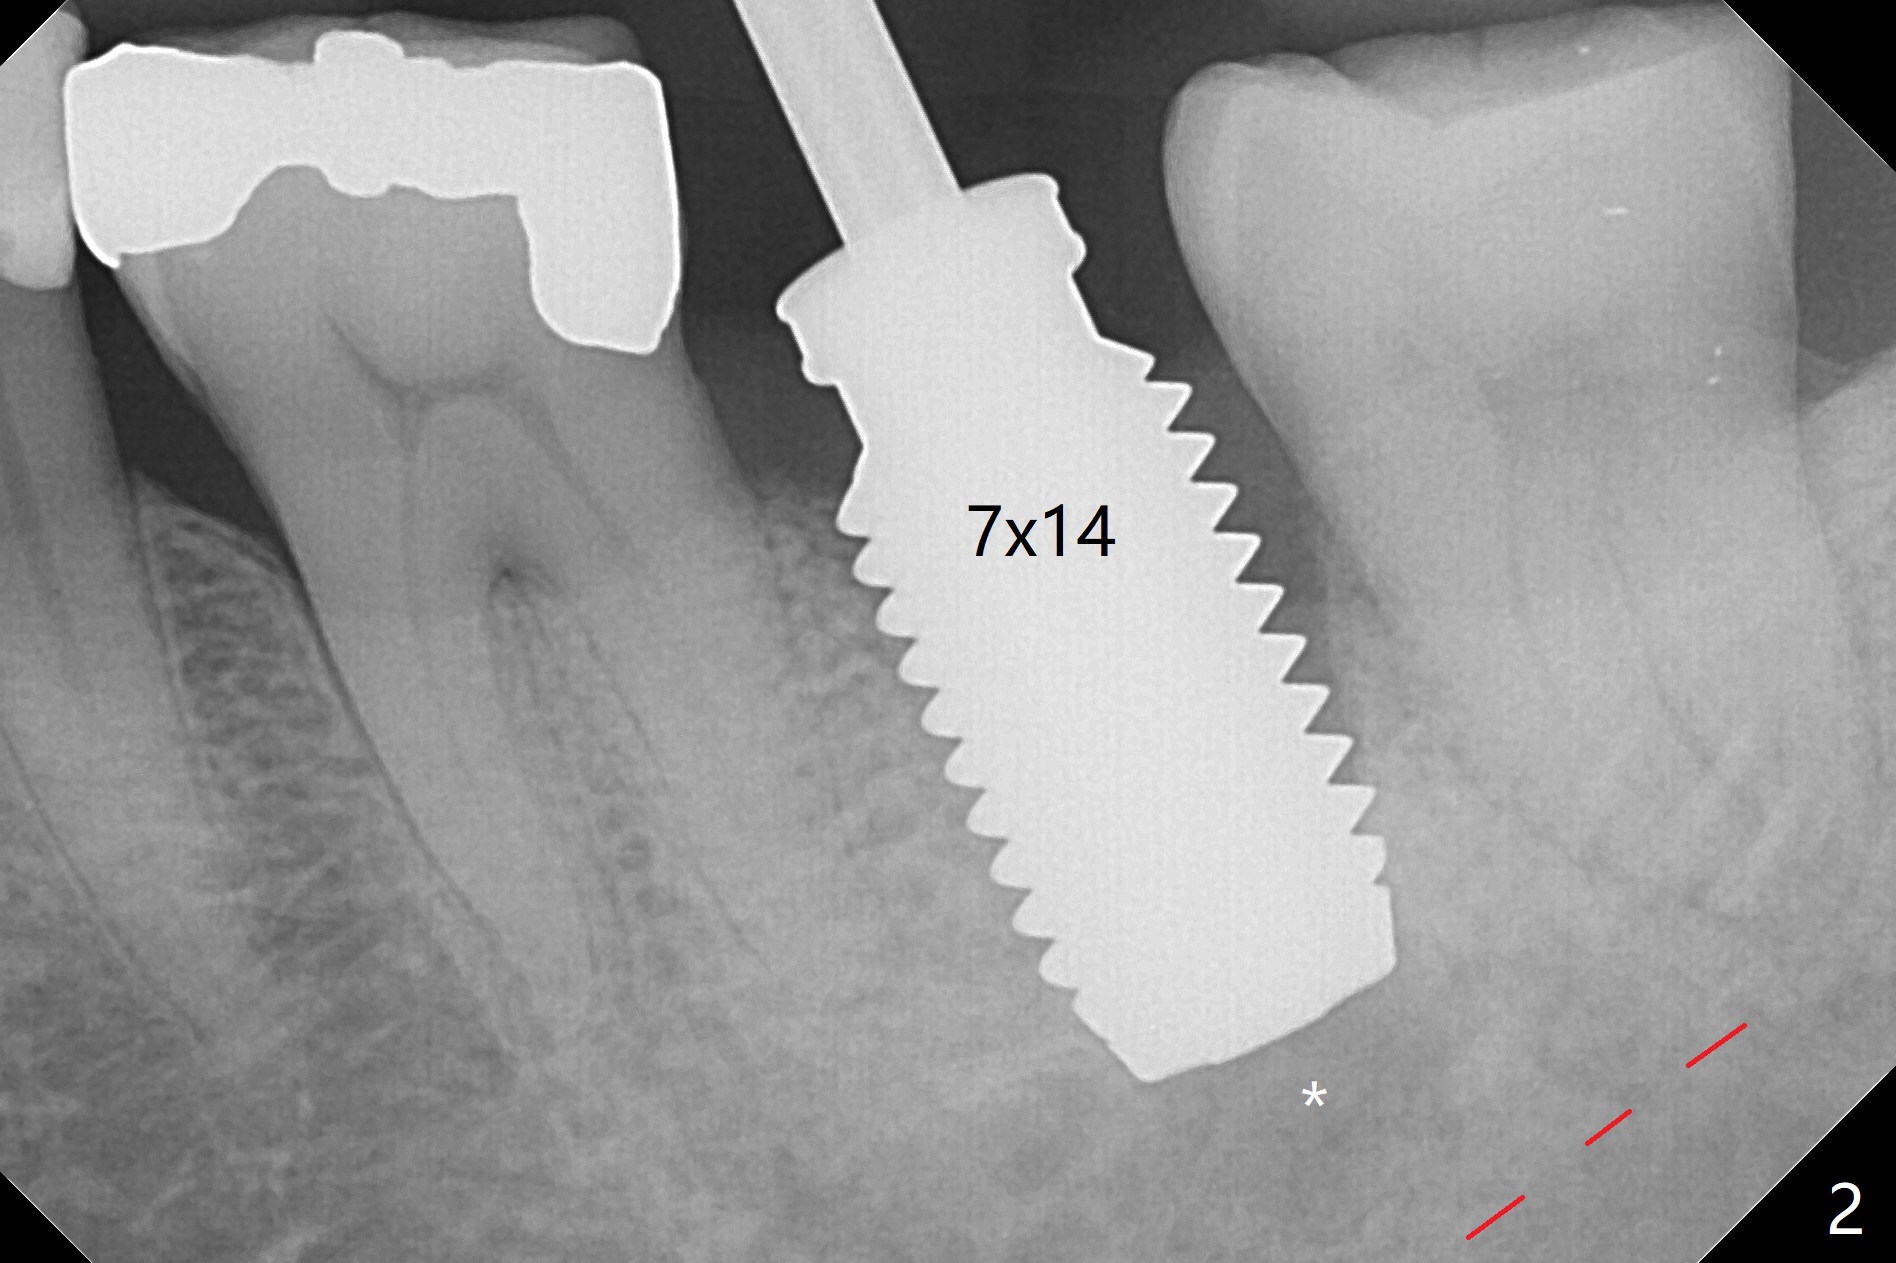

When the mobile tooth #18 with apical granulation tissue is extracted, the socket is large and long (close to the Inferior Alveolar Canal (Fig.2,3 red dashed line). Without drilling, a 7 mm bone level tap does not obtain stability. A 8x17 mm tapered tap reaches the bottom of the socket with minimal stability, but coronally it is close to the tooth #32 (Fig.1). When a 7x14 mm cylindrical tap is placed, it is shy of the bottom of the socket (Fig.2 *), but the trajectory improves. A 7x14 mm tissue-level implant is placed with ~45 Ncm (still not secure) with Vanilla graft placed mainly distolingually (Fig.3). With the large implant, the socket is closed 8 days postop (Fig.4). The soft and hard tissues appear to heal 3 months postop (Fig.5,6). A healing abutment (Fig.7 H) is placed to push the mesial papilla mesially (*). Two weeks later impression is taken with ease because of the healing abutment. There is no bone loss 4.5 months postop (immediately post cementation, Fig.8).